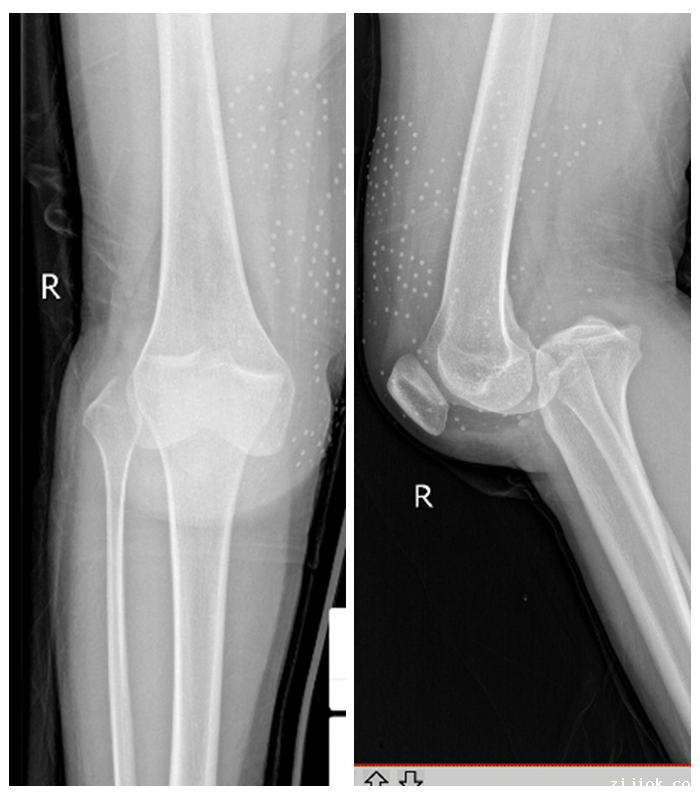

4周前,28岁的李女士因车祸导致右膝关节严重脱位,这是一件不幸的事情,然而祸不单行,在检查中,不仅发现了右膝关节处的前后交叉韧带断裂,而且内侧半月板桶柄样也同样撕裂了,这属于膝关节韧带损伤最严重的类型。

因患者右膝关节损伤严重,骨一科黄斌副主任医师组织了科内疑难病例讨论,为患者制定了详细的手术计划,决定为其采用关节镜下膝关节清理、人工韧带重建、半月板修复术。